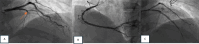

Fig. 6

Immediate invasive strategy procedure. a A diagnostic angiography revealed total occlusion at the proximal LAD with TIMI flow 0 (red arrow). b RCA was dominant, with diffuse stenosis at 70% in the mid. c Successful PCI with implantation of 3.5 × 38 mm coronary stent and 2.5 × 32 mm coronary stent was performed with the result TIMI flow 3